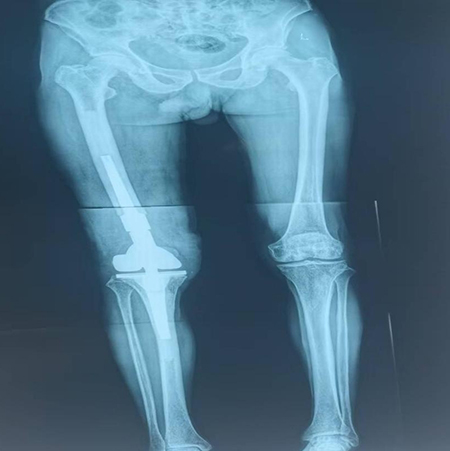

术后双下肢全长片

术后第一天,陈大爷的疼痛明显缓解,家属悬着的心也终于放下了。在李洁护士长及科室护理团队的精心照料和指导下,术后第三天,陈大爷就逐步开始了膝关节功能锻炼。从最初的床上活动到后来的下床行走,康复训练循序渐进,每一点进步都离不开陈大爷的坚持和医护人员的辛勤付出。经过一段时间的康复,陈大爷的膝关节功能逐渐恢复,疼痛感消失,行走能力得到了显著改善。出院时,他已经能够不需要拐杖辅助,独立行走。